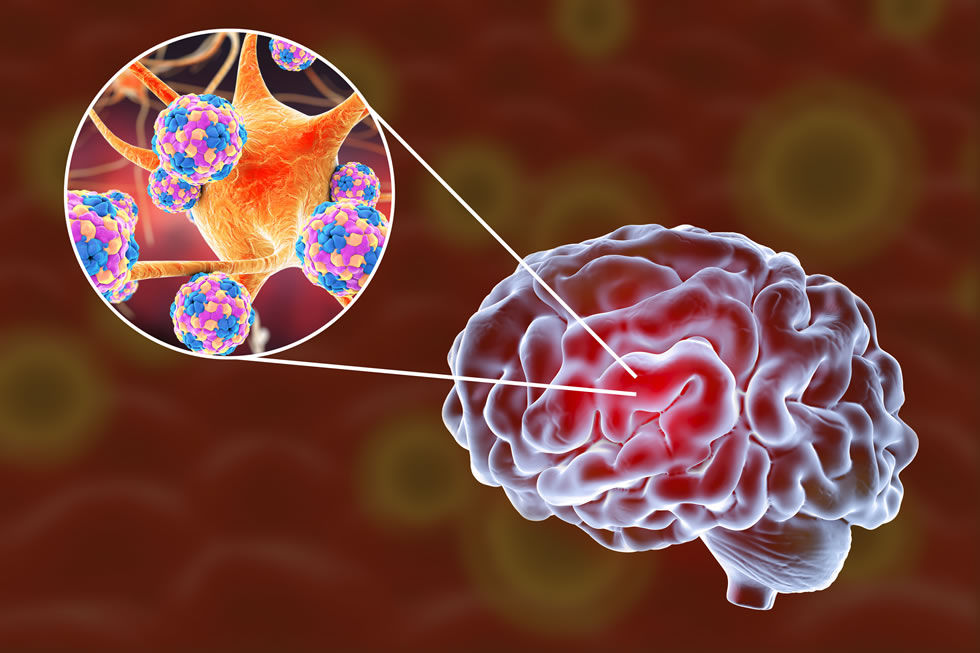

Τόσο η εγκεφαλίτιδα, όσο και η μηνιγγίτιδα είναι λοιμώξεις του εγκεφάλου, αλλά επηρεάζουν διαφορετικά μέρη του.

Η μηνιγγίτιδα είναι μια λοίμωξη στις μεμβράνες που περιβάλλουν τον εγκέφαλο και το νωτιαίο μυελό (μήνιγγες). Η εγκεφαλίτιδα είναι φλεγμονή των εγκεφαλικών ιστών.

Και οι δύο καταστάσεις μπορούν να προκληθούν από ιούς και βακτήρια. Αλλά η εγκεφαλίτιδα θα μπορούσε επίσης να προκληθεί από μια αυτοάνοση απόκριση και η μηνιγγίτιδα θα μπορούσε επίσης να προκληθεί από τραυματισμούς, καρκίνο, λύκο και ορισμένα φάρμακα.